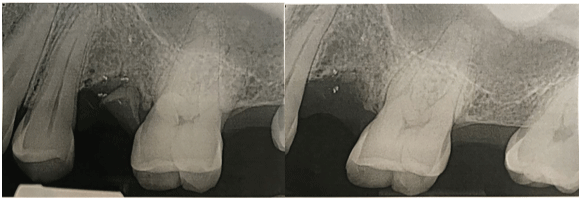

2016年11月初,患者在第二次初级保健医生就诊后的一天内前往当地牙医诊所就诊。进行了全面的临床评估和影像学检查(图1)。患者没有出现面部不对称或面部皮肤变化。口腔内检查显示口腔黏膜正常完整,口腔内结构解剖正常。刺激后上颌后左象限牙齿热测试结果为阴性,叩诊测试结果为非局部性轻度压痛。患者牙周健康,口腔卫生良好。除上颌左第二前磨牙根无症状保留外,临床上无明显龋损(#13)。矫形断层扫描显示双侧上颌窦无浑浊,上颌牙槽骨水平在正常范围内,冠状面内没有显示龋病或相关的根尖周放射透度。根尖解剖正常,无吸收、扩口或移位。x线片上发现残留根#13,根尖周无相关的放射透光度

图1:前处理矫形图显示清晰的上颌窦,在左上颌后牙槽骨段无骨透光性。冠内或根尖周无放射透光度。牙槽骨水平在正常范围内。

经过临床检查和适当的影像学检查,确定其表现的症状是非牙源性起源,可能是上颌窦起源。治疗建议是由口腔和颌面外科医生进行手术摘除保留根#13。取药前给予1周疗程的抗生素治疗(阿莫西500mg b.i.d × 7天)。保留的#13根被平安无事地取出(图2),如果症状持续,建议患者寻求耳鼻喉科专家的进一步评估。

图1:(左)拔牙前和(右)拔牙后保留的13号根尖的根尖周x线片。周围牙槽骨正常的小梁结构。